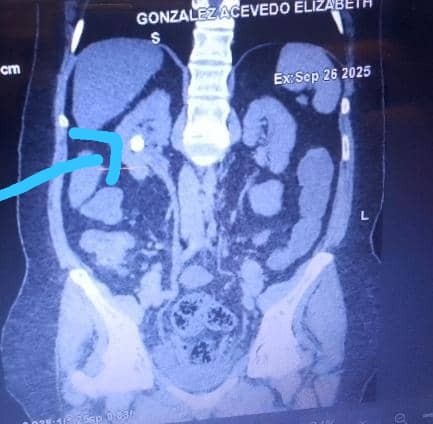

Hoy Elizabeth necesita con urgencia una cirugía llamada Nefrolitotomía Percutánea Derecha, ya que presenta una calcificación en el cáliz superior central del riñón derecho. Esta afección le causa dolores intensos, inflamación en las piernas y pies debido a la retención de líquidos, y un deterioro progresivo en su función renal.